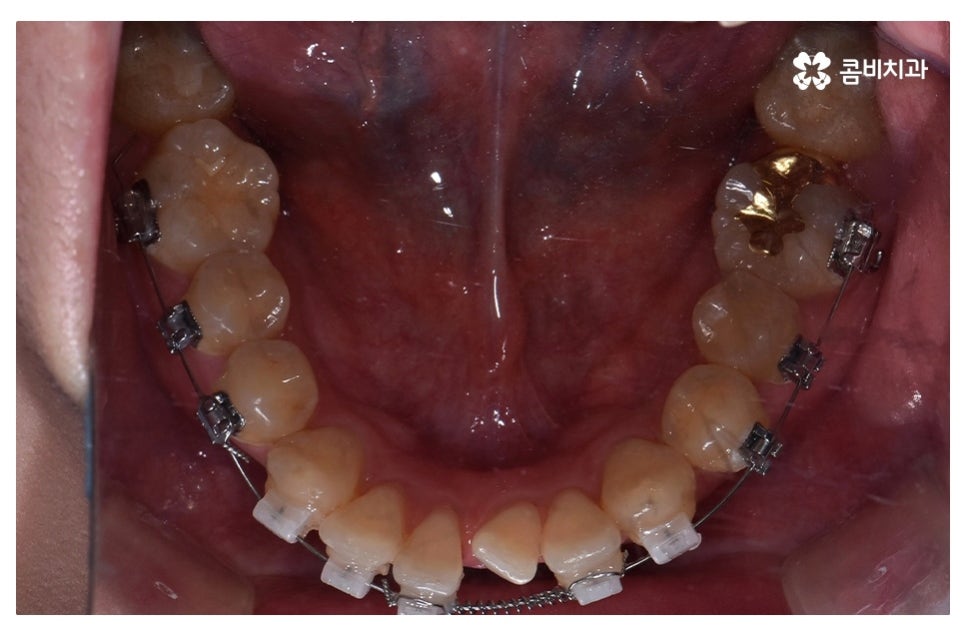

이번 포스팅에서 보인 덧니교정 사례의 경우 기능이 적은 작은 어금니를

발치하여 교정이 진행되었으며 발치를 진행하는 경우

작은 어금니를 발치하는데 충치 등으로 인해 손상이 큰 치아를

발치하는 경우가 일반적이라고 할 수 있어요.

요즘은 교정 장치의 선택에 있어서 다양한 선택이 가능하지만

보편적으로는 본 포스팅의 사례처럼 클리피씨 교정이 많이 선호되고 있어요.

클리피씨 교정은 일반적인 교정보다 치료 기간을 단축시킬 수 있고

통증이 비교적 적으며 세라믹 재질로 심미적이라는 장점이 있어요.